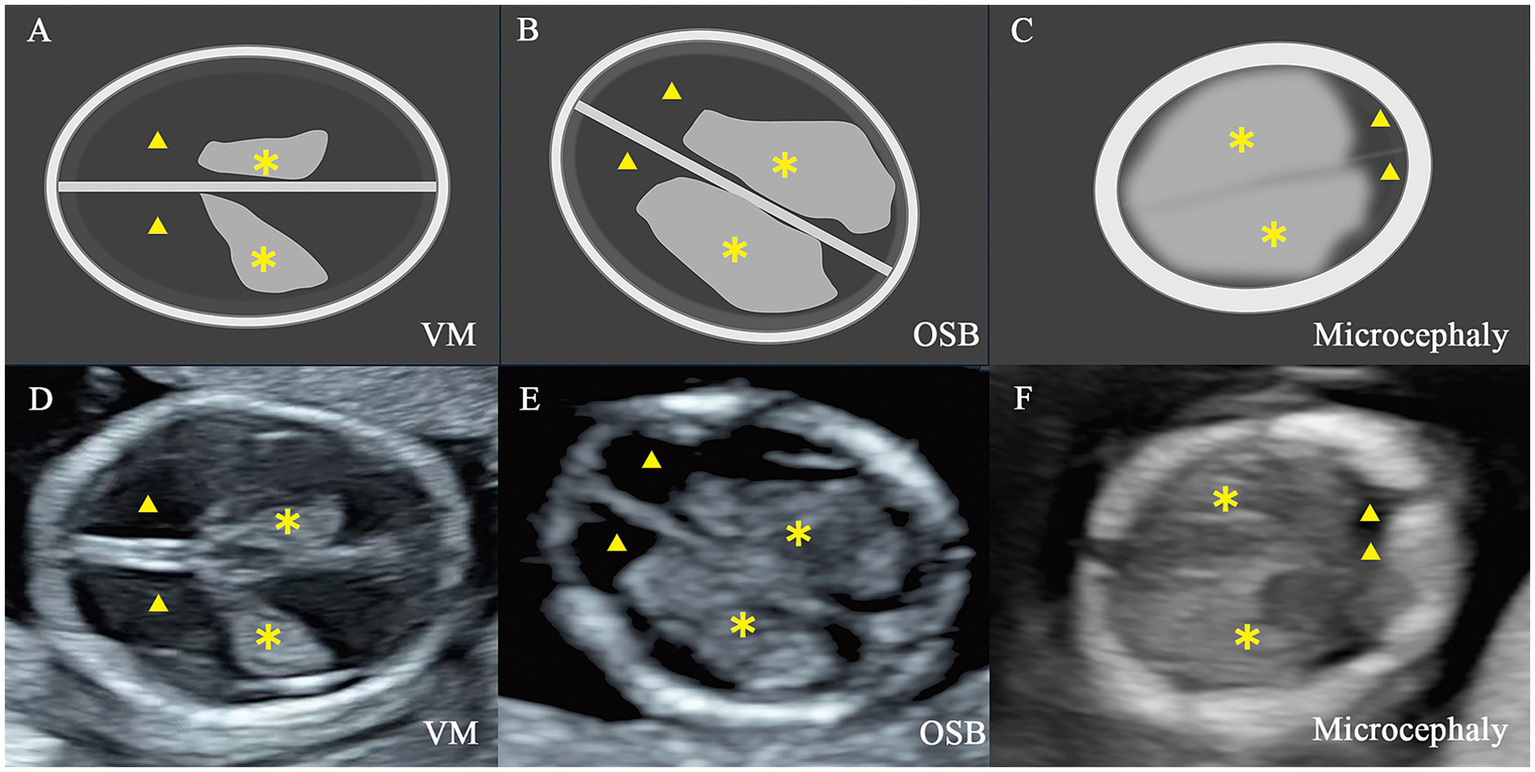

Figure 2

Illustration and two-dimensional view of the standard axial butterfly plane in fetus with nervous system abnormalities. (A,D) Fetus with ventriculomegaly (VM). (B,E) Fetus with open spina bifida (OSB). (C,F) Fetus with microcephaly. ▲, the lateral ventricles; ✽, the choroid plexus.